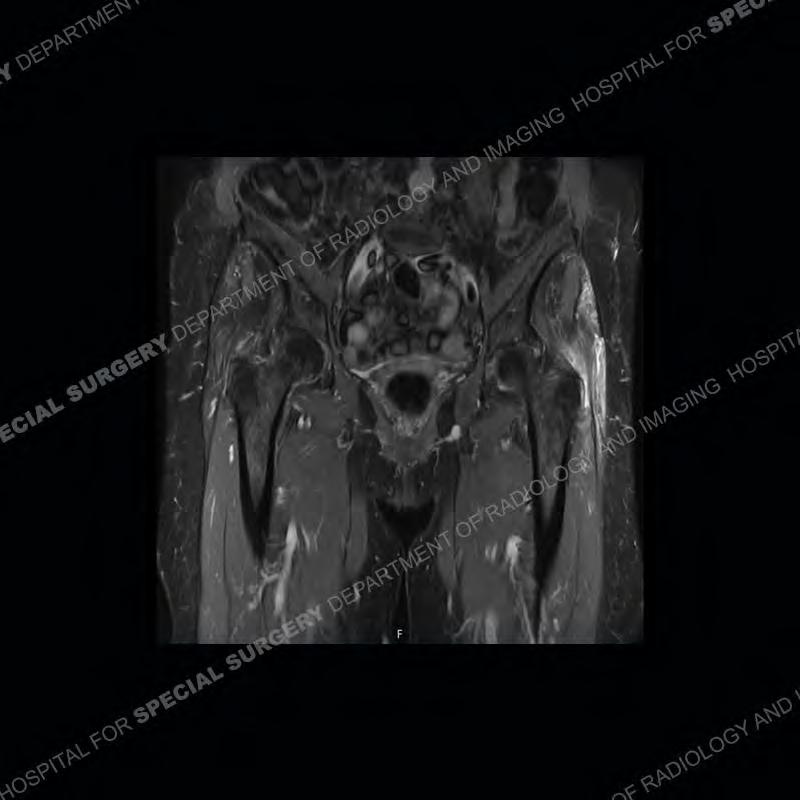

The radiograph is not particularly contributory in this case. The MRI demonstrates markedly abnormal architecture of the gluteus minimus and anterolateral band of the gluteus medius. Portions of the tendons are high signal, portions are highly attenuated, and portions are disrupted. A large, complex fluid collection is present in the adjacent soft tissue.

Diagnosis: Gluteal Tendinosis and Disruption with Complex Trochanteric Bursal Collection

Not as much of a diagnostic dilemma as many of the other cases shown but just a nice example of the pathology seen of the gluteal tendons and a cause of trochanteric pain. Although, frequently thought of in isolation, trochanteric bursitis or bursal thickening is much more commonly a reactive change to underlying pathology of the subjacent gluteal tendons. The gluteus medius is divided into a posterior band and an anterolateral band. Tendinosis and partial tearing very commonly will involve the gluteus minimus and especially the more posterior fibers and then propagate into the anterior lateral band of the gluteus medius. Involvement of the posterior band of the medius is much less common and engenders a marked degree of functional impairment.

The bursae about the greater trochanter can be a little bit confusing especially given the terminology. Trochanteric bursitis is implied to mean the subgluteus maximus bursa which is present deep to the maximus and just lateral/superficial to the trochanter. That is the bursa involved in this case. In this case the complexity of the bursa relates to the tendon tearing with inflammatory change and probably hemorrhage accounting for the complexity. Two other, less frequently involved bursa are also present. The subgluteus medius and subgluteus minimus bursa are found just deep to the named tendons. Although pathology does frequently follow the previously described pattern it is possible to have isolated pathology to either the medius or minimus.